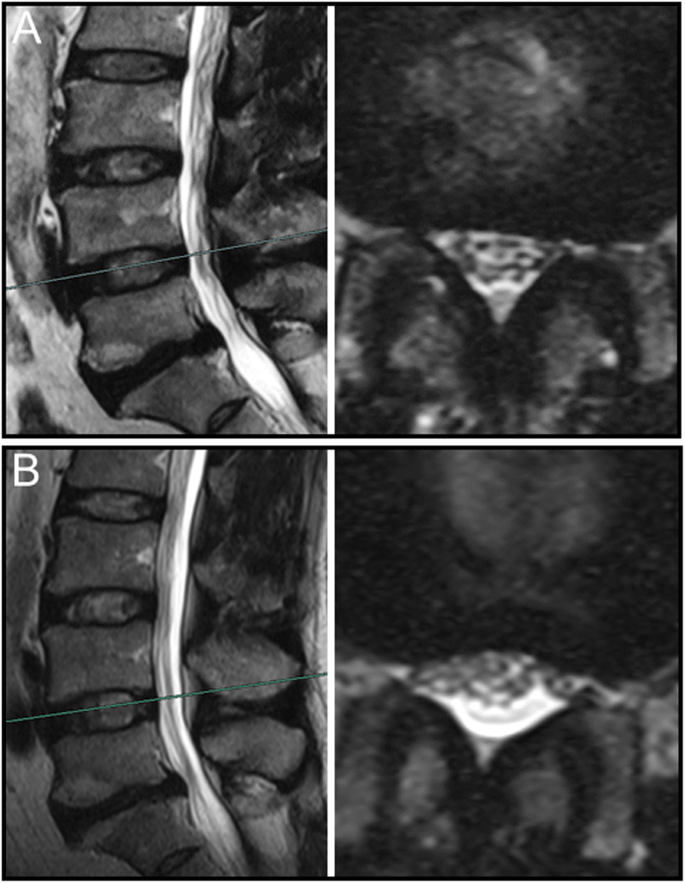

The sedimentation of nerve roots on MR images of various body position

Overall, nerve roots of 48 (85.7%) patients subsided to the ventral side of the dural sac on the prone MR images, although that of 8 (14.3%) patients remain stay in the dorsal side of dural sac. Of the 25 patients with a negative SedSign on supine MR images, the nerve roots settled to the ventral side of the dural sac on prone MR images in 24 patients (Fig. 1). Nerve roots in the remaining 1 patient, who was diagnosed as disc herniation, did not settle to the ventral dural sac (Fig. 2). For all the 31 patients with a positive SedSign, nerve roots subsided to the ventral side of the dural sac on the prone MR images in 24 patients (Table 2, Fig. 3). The nerve roots of the other 7 patients still stay (sequester) in the dorsal dural sac, which were due to single level (Fig. 4) or multiple level stenosis (Fig. 5). The nerve roots in patients with positive SedSign were more likely to stay in the dorsal dural sac on prone position MR images (22.6% vs 4%, P < 0.05, Table 2). In addition, the nerve roots subsided to the left dural sac in all the 5 patients when they were MR imaged on a left lateral position (Fig. 6).

The mechanism underlying nerve roots floating in the spinal canal against gravity remains unclear. We postulated that such an integrated force against gravity may result from multiple factors, including the length and tension of the nerve roots, the level of spinal stenosis, and the degree of lumbar lordosis. Alterations of these factors, as we clearly see, typically occurred in presence of degenerative changes in lumbar spine. In this study, positive SedSign on prone position MR images occurred mostly in multiple level spinal stenosis. In addition, the nerve roots in those case were tensioned (Fig. 5), which was also observed in the case with negative SedSign (Fig. 2). However, nerve roots did not subside in the direction of gravity despite loosen nerve roots in redundancy (Fig. 4). The role of tension in nerve roots sedimentation can be further studied using patients whose nerve roots tension is high, such as tethered spinal cord syndrome.